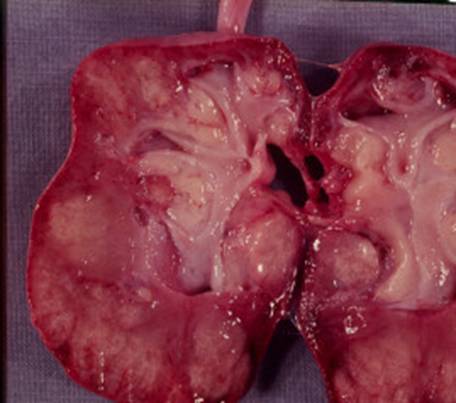

In pielonefrita acuta, mucoasa cailor urinare este inflamata, rinichii sunt mari si congestionati, la suprafata capsulei se intalnesc microabcese.

In formele cronice, rinichii sunt mici, atrofici cu cicatrici parenchimatoase care deformeaza suprafata renala, insotita de deformarea calicelor adiacente. Microscopic se observa o inflamatie acuta cu edem interstitial si infiltratie cu polimorfonucleare, neutrofile.

Pielonefrita cronica a rinichiului